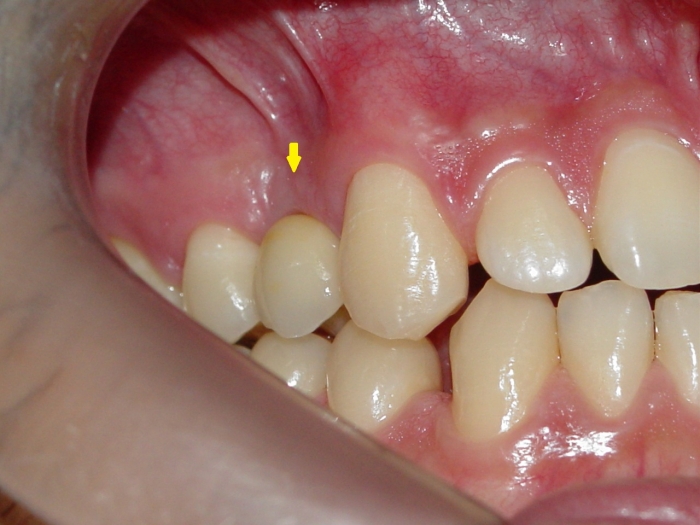

Clique nas imagens para ampliar